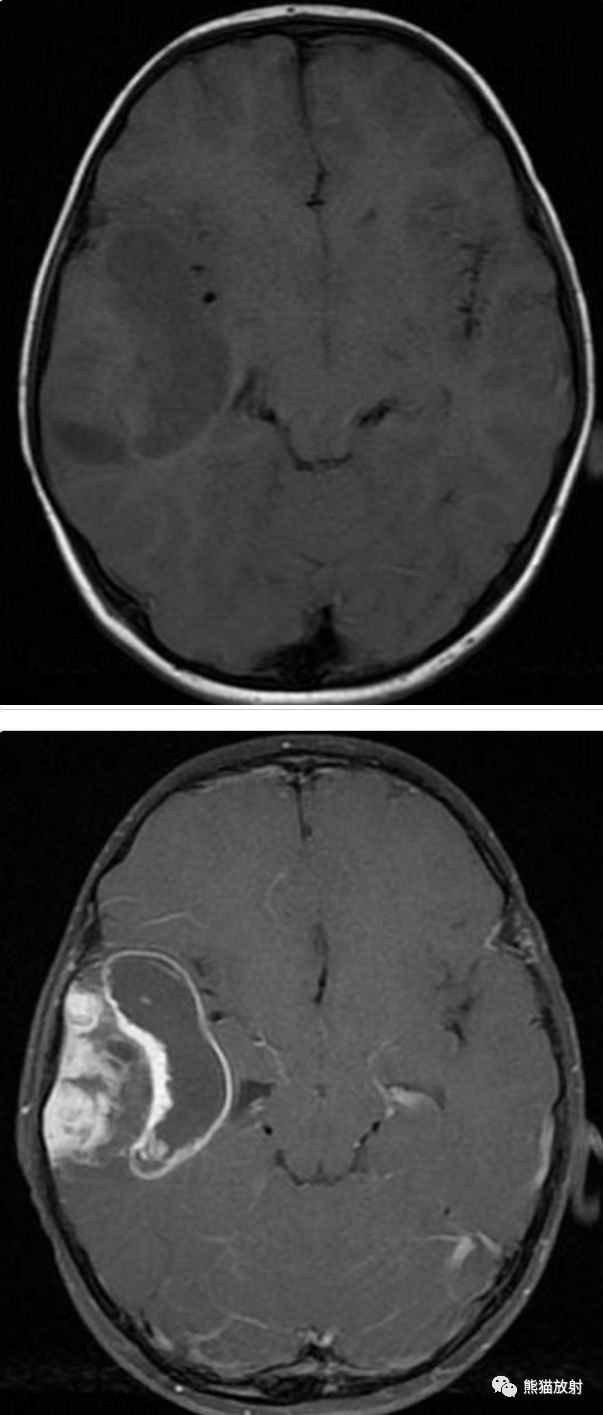

男性,14岁,癫痫发作数月。

⭐️ 多形性黄色星形细胞瘤

Pleomorphic xanthoastrocytoma

青少年 癫痫 颞叶 囊实性占位 病灶表浅 累及脑膜 实性部分位于脑表面 明显强化